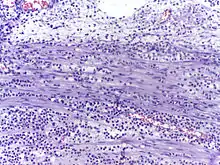

![]() | Neutrophils | Micrograph showing neutrophils in acute inflammation. | Category: Neutrophils | Neutrophil |